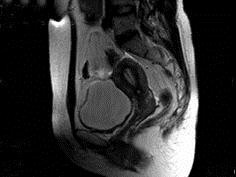

问题 女性,46岁,无任何不适,体检扪及盆腔包块,行MRI检查,如图所示,最佳答案是 ( )

选项 A、卵巢粘液囊腺瘤 B、卵巢结核 C、卵巢皮样囊肿 D、卵巢粘液癌 E、卵巢囊肿

答案 E